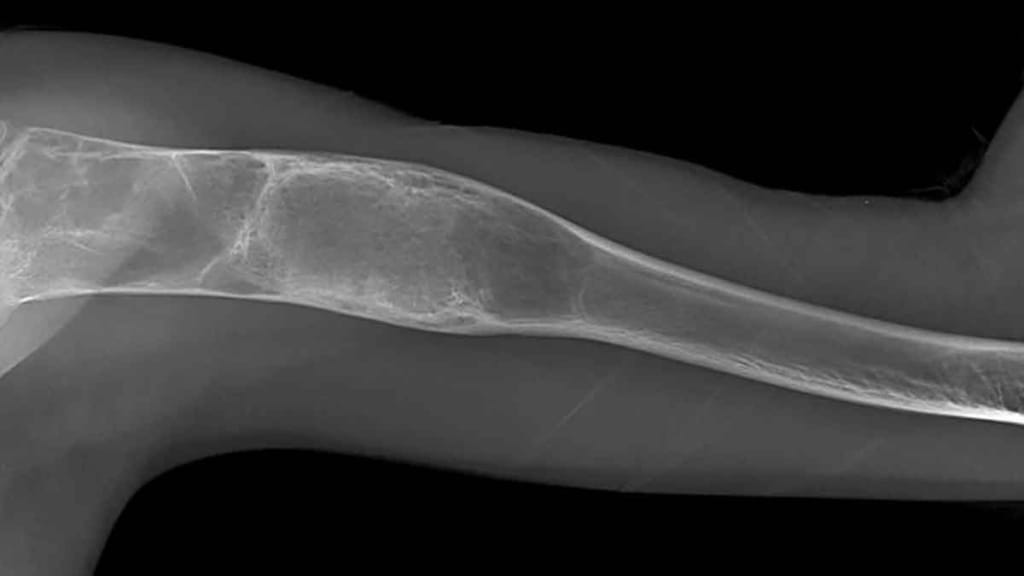

Tedavi sürecinin tümörün biyolojik yapısına, yerleşimine ve yayılım durumuna göre şekillendiğini kaydeden Doç. Dr. Ayas, iyi huylu tümörlerde genellikle daha sınırlı ve koruyucu cerrahi müdahalelerin yeterli olabildiğini söyledi. Kötü huylu tümörlerde ise tümörün yalnızca görünen kısmının değil, çevresindeki potansiyel riskli dokularla birlikte çıkarılmasının hayati önem taşıdığını ifade etti. Bu yaklaşımın, hastalığın tekrar etme riskini azaltarak uzun dönem tedavi başarısını artırdığını dile getirdi.

Ameliyat sonrası oluşan kemik ve doku kayıplarının modern rekonstrüksiyon yöntemleriyle başarıyla giderilebildiğini ifade eden Ayas, “Biyolojik teknikler, hastaya özel geliştirilen protezler ve kemik transferleri sayesinde hem anatomik bütünlüğü yeniden sağlıyor hem de hastalarımızın fonksiyonlarını en iyi şekilde korumayı hedefliyoruz” diye konuştu.